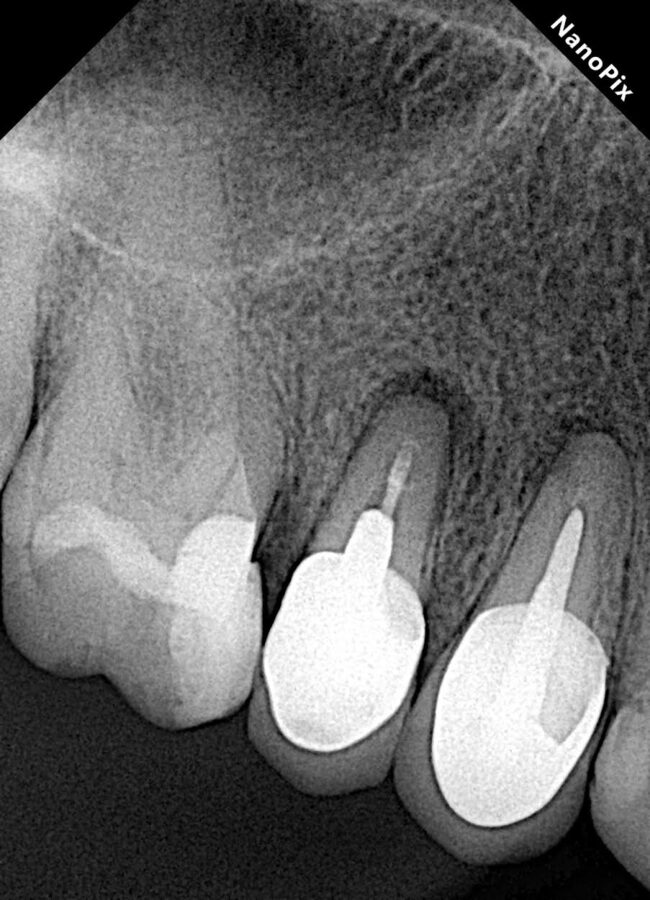

Dr. Marc Llaquet’s clinical case of a reendodontic tooth 2.4 instrumented with RetreatAll® files to remove gutta-percha in which ultrasonic activation was performed with Z-Activator® during irrigation.